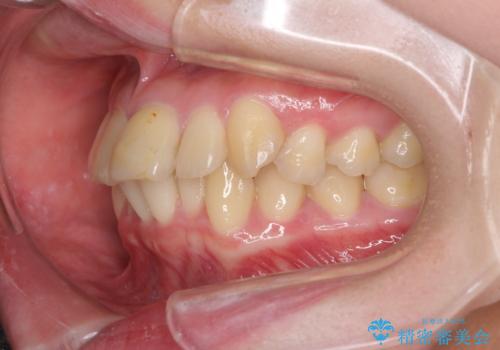

上下前歯のデコボコをきれいに インビザラインによる矯正治療

- 前歯の著しい叢生と前突感を気にして来院された患者様です。

叢生が強いため、事前に前歯をワイヤー矯正で速やかに叢生を解消し、その後はインビザラインにて矯正治療を行うこととしました。

ワイヤー矯正を併用したことで前歯の叢生を速やかに解消することができました。

一方口元の突出感を改善するために時間がかかり、2年超を要しましたが、満足のいく仕上がりとなりました。